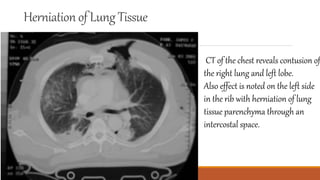

Bilateral traumatic pneumatoceles. CT scan

demonstrates bilateral cysts with air-fluid levels.

Bilateral traumatic pneumatoceles.CT scan demonstrates bilateral cysts with air-fluid levels.